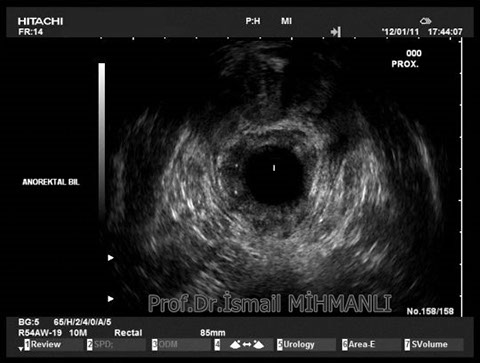

Transsfinkterik fistül

Fistüle makat kası hasarı eşlik ediyorsa endoanal US'de tespit edilir.